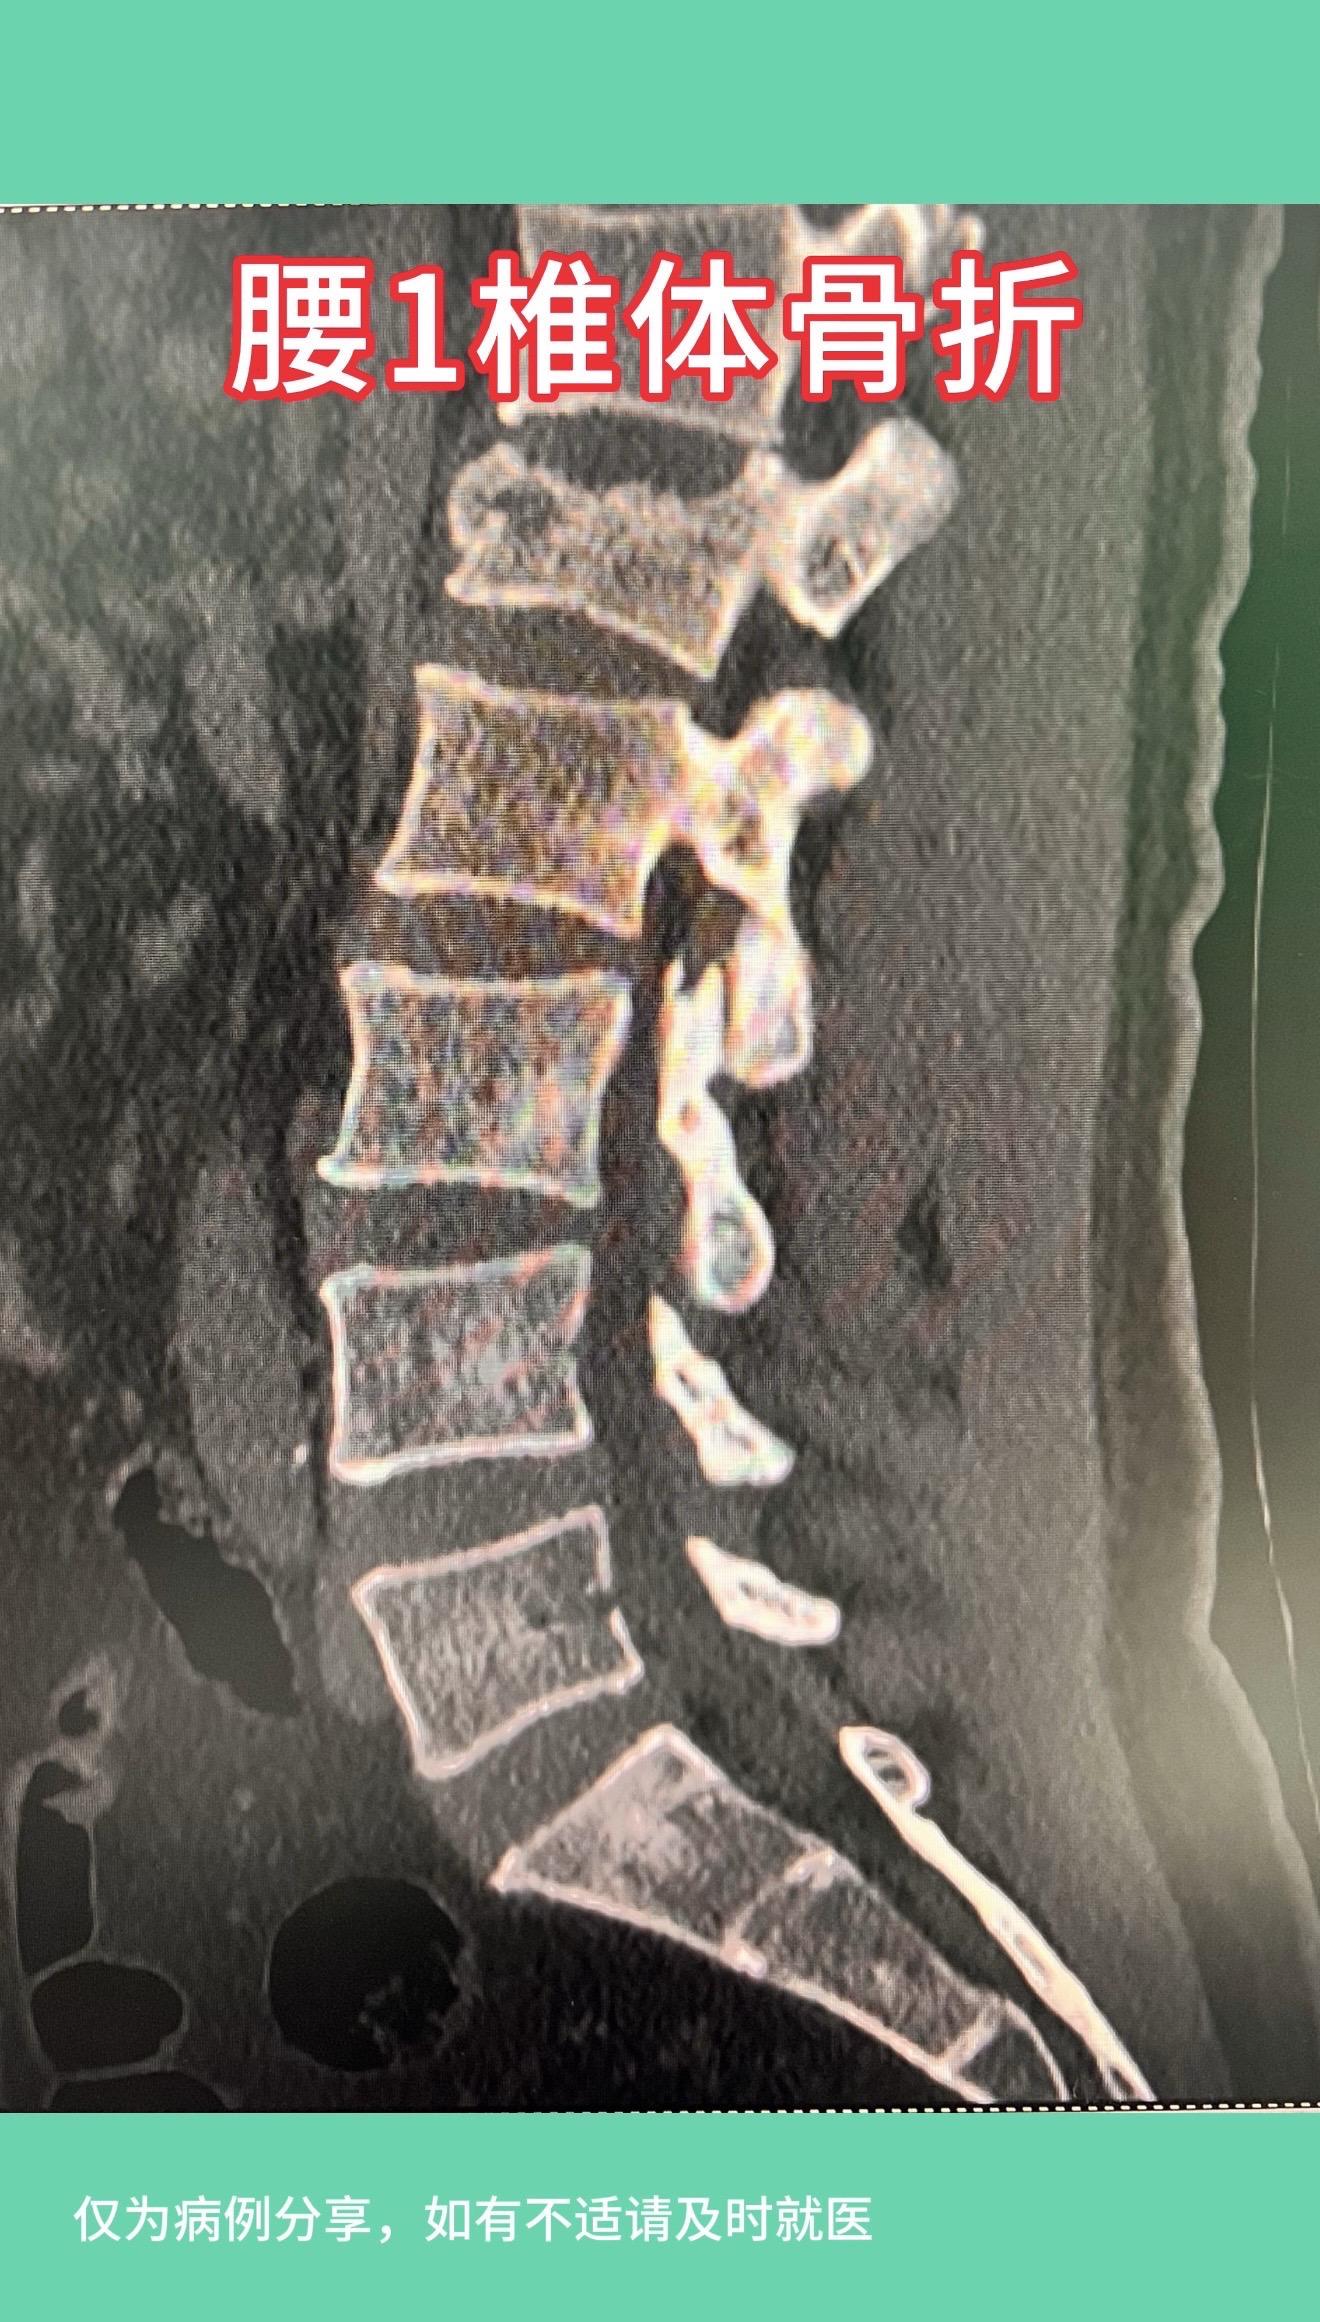

50多岁女性,在家干农活时从凳子上摔下,腰1椎体骨折,手术后复位理想...

50多岁女性,在家干农活时从凳子上摔下,腰1椎体骨折,手术后复位理想,愿患者早日康复